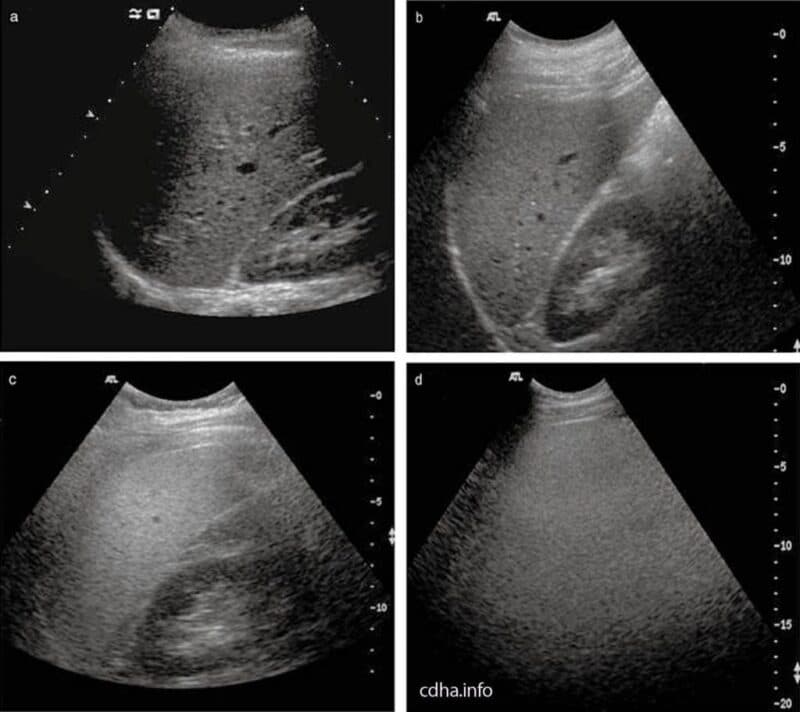

- Hình ảnh gan trên siêu âm: Siêu âm là phương pháp phổ biến để phát hiện gan nhiễm mỡ độ 2. Hình ảnh cho thấy gan tăng độ sáng rõ, cấu trúc gan kém đồng nhất và mức độ mỡ nhiều hơn so với độ 1. Dù không xác định chính xác tỷ lệ mỡ, siêu âm vẫn giúp phân biệt các mức độ gan nhiễm mỡ.